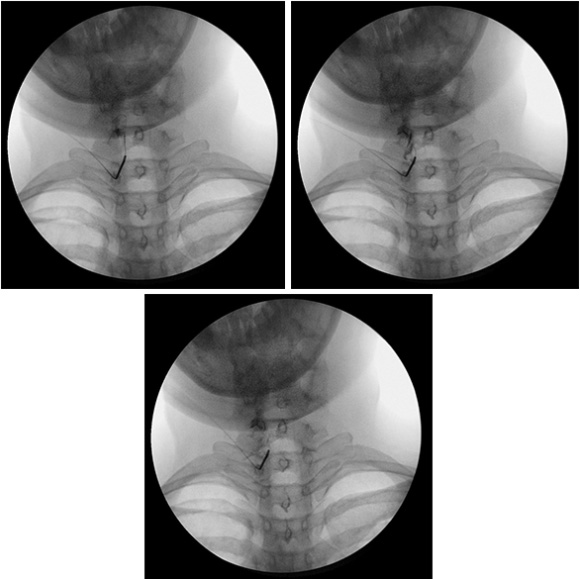

경막외 감압술은 척추 질환의 대표적인 비수술 치료법으로 작은 관을 이용하여 지름 1~2mm 정도의 얇은 관을 꼬리뼈쪽으로 삽입한 후 디스크나 신경의 염증이 있는 부위에 약물을 투여하는 치료법입니다.

신경의 압박을 풀어주고 염증과 유착을 제거하여 신경 주변의 혈액순환을 개선하는 시술 방법입니다.